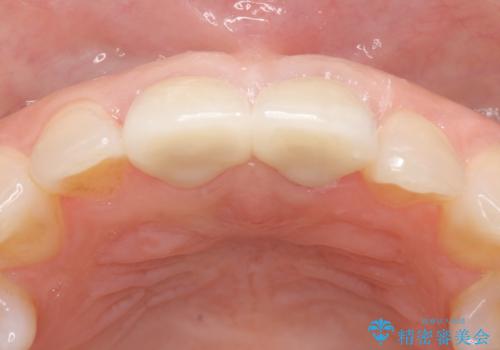

オールセラミッククラウン 変色が気になる前歯の治療

- 前歯の変色が気になるのでセラミックによる治療を行いたいといらっしゃった方の症例です。

左上1番目の歯の再根管治療終了後、左右1番目の2歯をオールセラミッククラウンで補綴しました。